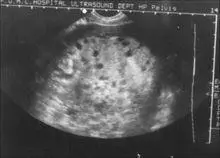

滋养细胞肿瘤